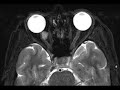

Orbital Hemangioma

There is a T1 hypointense, minimally T2 hyperintense ovoid intraconal mass in the medial aspect of the right orbit. Contrast was not administered for this exam, but subsequent studies showed avid enhancement. This lesion is compatible with an orbital hemangioma. These lesions represent cavernous venous malformations which have a pseudocapsule. They are usually intraconal as seen here and more commonly in the lateral orbit. It is the most common adult orbital mass lesion.